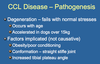

List the Factors playing a Role in Pathogenesis of Chronic Cranial Cruciate Ligament Disease

Degeneration of Cranial Cruciate Ligament Occurs with Age- This Degeneration tends to be worse in Larger Dogs (Over 15 kg/ 30lbs)

Factors that Contribute to Degeneration:

Obesity/Poor Fitness- More Stress/Strain on Ligaments

Conformation- Conformation of Femur, or even Stance/Gait would place Additional Stress on the Ligament

Excessive Plateau Angle- If the Slope is Steeper, the CCL would be under Greater Strain